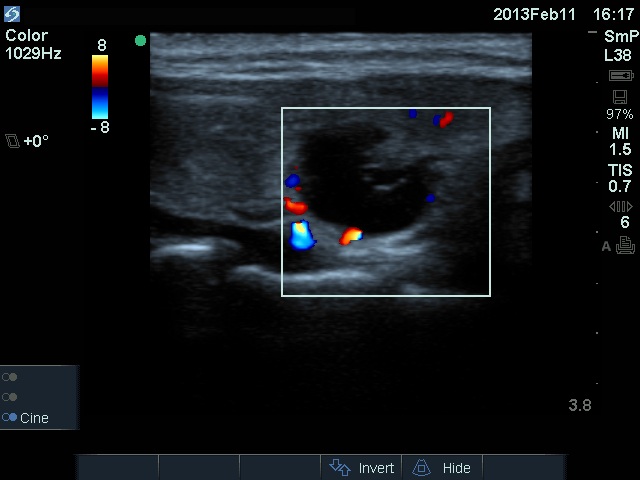

Ultrasonography: The right thyroid was echonormal and contained several small, insignificant lesions. There was a hypoechogenic lesion with blurred borders in the central and in the ventro-medial part of the left thyroid with increased intranodular blood flow.

The ultrasound pattern of de Quervain's thyroiditis and that of papillary cancer are very similar: a hypoechogenic lesion with blurred borders are found in both cases. They differ in vascularization statistically but the vascular pattern has only limited practical significance. In the acute phase of de Quervain's thyroiditis the vascularization is generally decreased but even in this case the situation was the opposite. The finding of not one but multiple hypoechogenic areas favored the possibility of subacute thyroiditis.

11 months after init. investig. |

7.30 |

0.18 |

4 months after delivery |